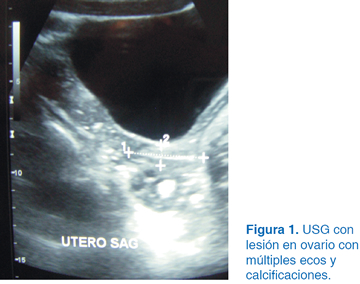

A los dos años del evento quirúrgico en el USG se apreció una tumoración en el ovario izquierdo con dimensiones de 10 x 12 cm (Figura 1). Se solicitó tomografía axial computarizada (TAC), observándose tumoración con densidades mixtas con diagnóstico probable de teratoma (Figura 2). Se optó por laparotomía exploradora donde se identificó el útero y se apreció tumoración dependiente de ovario izquierdo (Figura 3). Se realizó planeación de incisión (Figura 4), posteriormente tumorectomía (Figura 5) y salvamento de tejido ovárico (Figura 6). El reporte transoperatorio mostró teratoma monofásico con bordes libres de tumor.